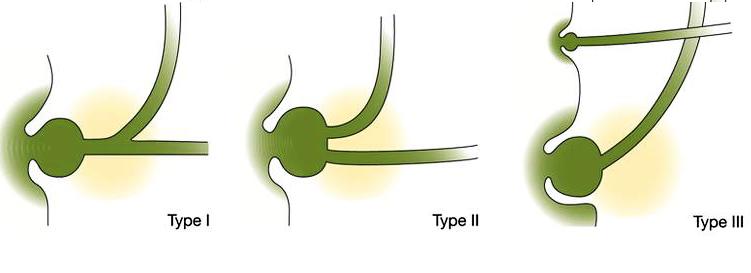

La situation du canal choledoque dans

ampoule Water , generalement peu en divise en troi type .

Type I , C'est abouchement du canal choledoque dans ampoule

hepato-pancreatique ( ampoule water) par un abouchement

commune a incidence 85,5% des cas . Type II ( 5,5% des cas )

c'est abouchement separe de ces deux canaux dans la papille

duodenal majeure . Type III a incidence de 9% des cas :

c'est le conduit pancreatique principale s'abouche au niveau

de la papille duodenale mineure et le canal choledoque en

accessoire avec un autre conduit abouche dans la papille

majeure .